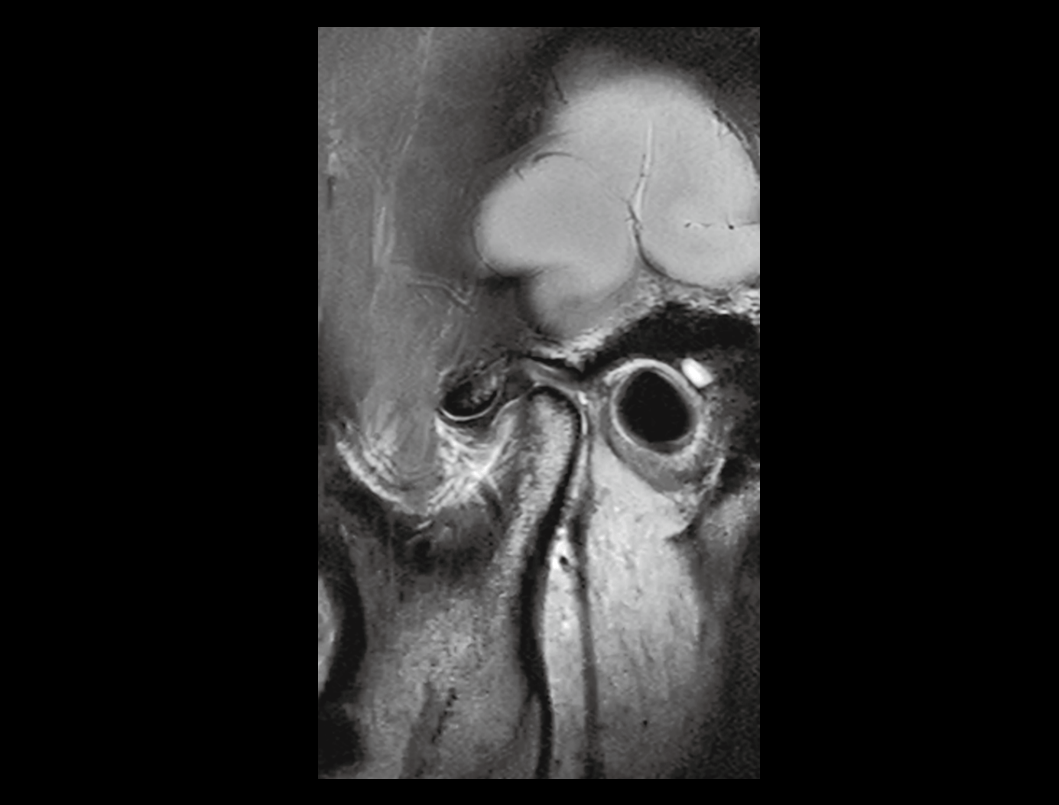

TMJ

Gleznă